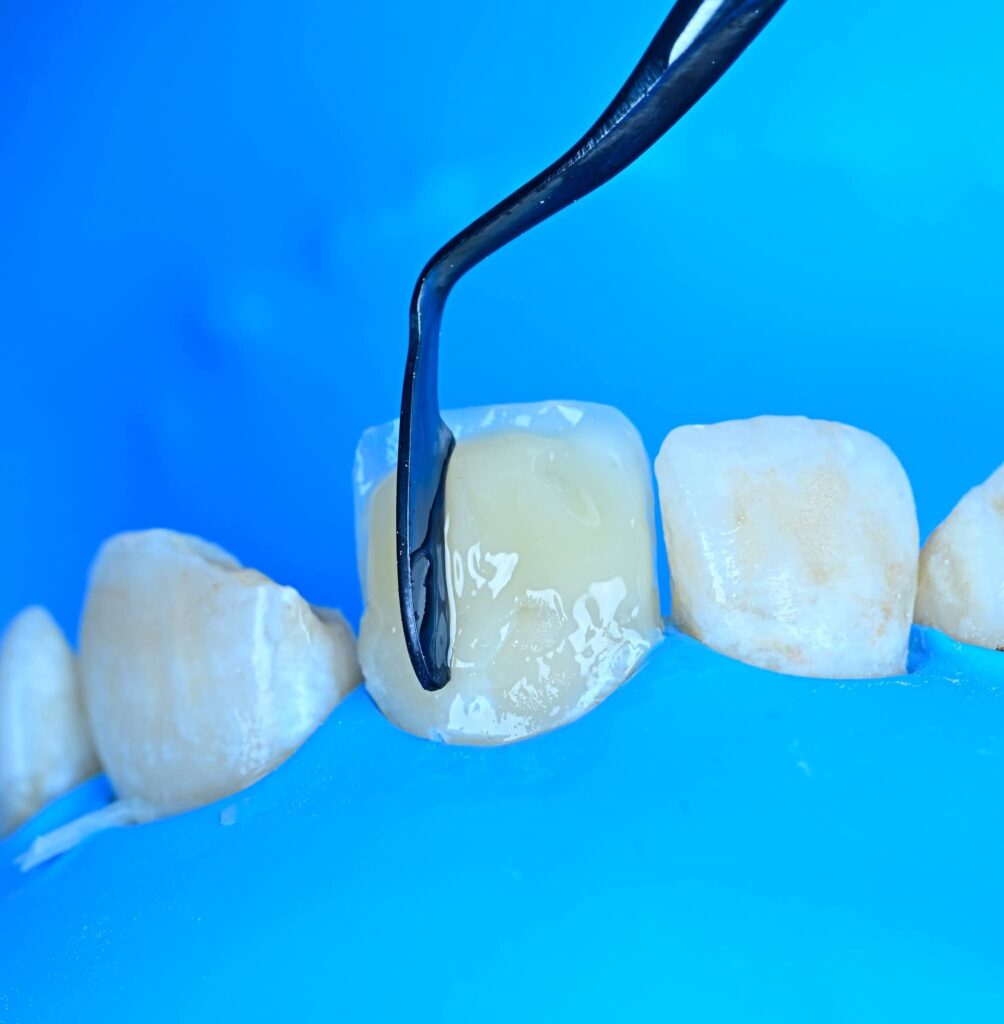

Symmetry and proportionality are fundamental principles in aesthetic dentistry, particularly in direct composite veneers, where the clinician acts simultaneously as a scientist and an artist. Successful veneers are not determined only by color and shape, but by the harmony between teeth, gingiva, lips, and face.

1. Tooth dominance (central incisors dominant)

Progressive embrasure increase from central to canine

2. Line angle positioning to control perceived tooth width

3. Surface texture and light reflection

4. Incisal translucency and halo effects